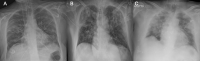

Results: Patients that had a RT-PCR positive for COVID-19 infection were 234 in total: 153 males (65.4%) and 81 females (34.6%), with a mean age of 66.04 years (range 18-97 years). Thirteen CXRs were negative for radiological thoracic involvement (5.6%). The following alterations were more commonly observed: 135 patients with lung consolidations (57.7%), 147 (62.8%) with GGO, 55 (23.5%) with nodules and 156 (66.6%) with reticular-nodular opacities. Patients with consolidations and GGO coexistent in the same radiography were 35.5% of total. Peripheral (57.7%) and lower zone distribution (58.5%) were the most common predominance. Moreover, bilateral involvement (69.2%) was most frequent than unilateral one. Baseline CXR sensitivity in our experience is about 67.1%. The most affected patients were especially males in the age group 60-79 years old (45.95%, of which 71.57% males). RALE score was slightly higher in male than in female patients. ANOVA with Games-Howell post hoc showed significant differences of RALE scores for group 1 vs 3 (p < 0.001) and 2 vs 3 (p = 0.001). Inter-reader agreement in assigning RALE score was very good (ICC: 0.92-with 95% confidence interval 0.88-0.95).

Conclusion: In COVID-19, CXR shows patchy or diffuse reticular-nodular opacities and consolidation, with basal, peripheral and bilateral predominance. In our experience, baseline CXR had a sensitivity of 68.1%. The RALE score can be used in the emergency setting as a quantitative method of the extent of SARS-CoV-2 pneumonia, correlating with an increased risk of ICU admission.